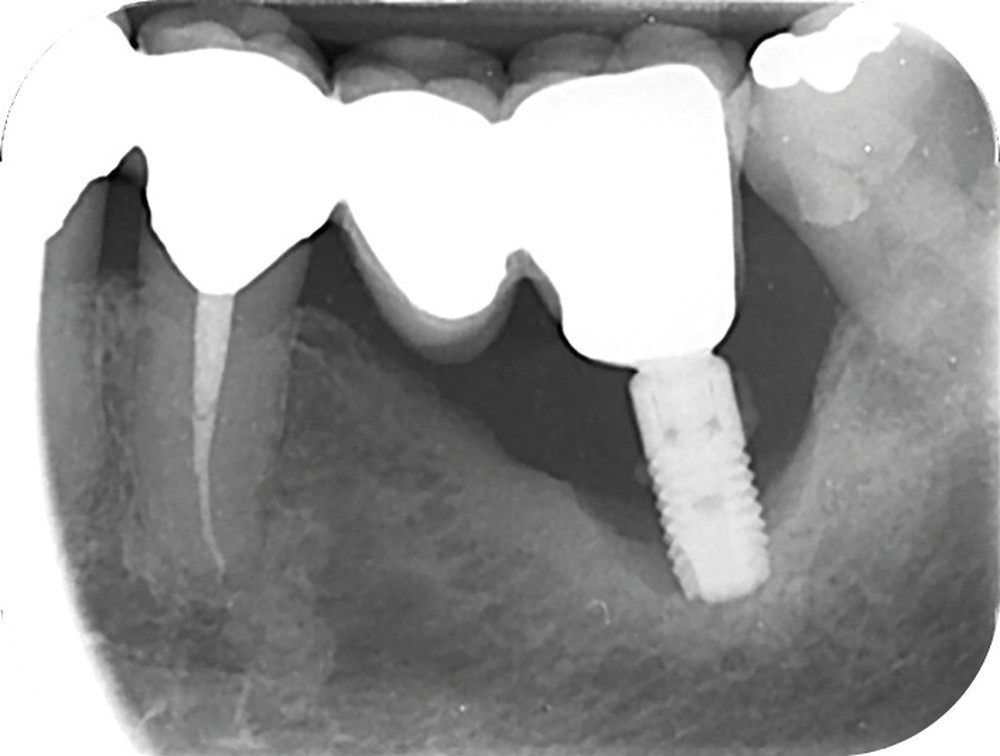

Le mode d’assemblage (prothèse vissée ou scellée) retenu peut aussi influencer la survenue d’une péri-implantite, avec une corrélation importante entre survenue de péri-implantite et présence d’excès de ciment de scellement [13, 14]. Une connexion dent-implant (prothèse dento-implanto-portée) est à proscrire, car plus propice aux péri-implantites et échecs mécaniques (fig. 4 et 5) [15, 16].

Le nombre d’implants influe aussi sur la survenue de péri-implantite. Dans les reconstructions plurales, l’implant médian est plus à risque de perte osseuse marginale et de péri-implantite [17] (fig. 6 et 7).